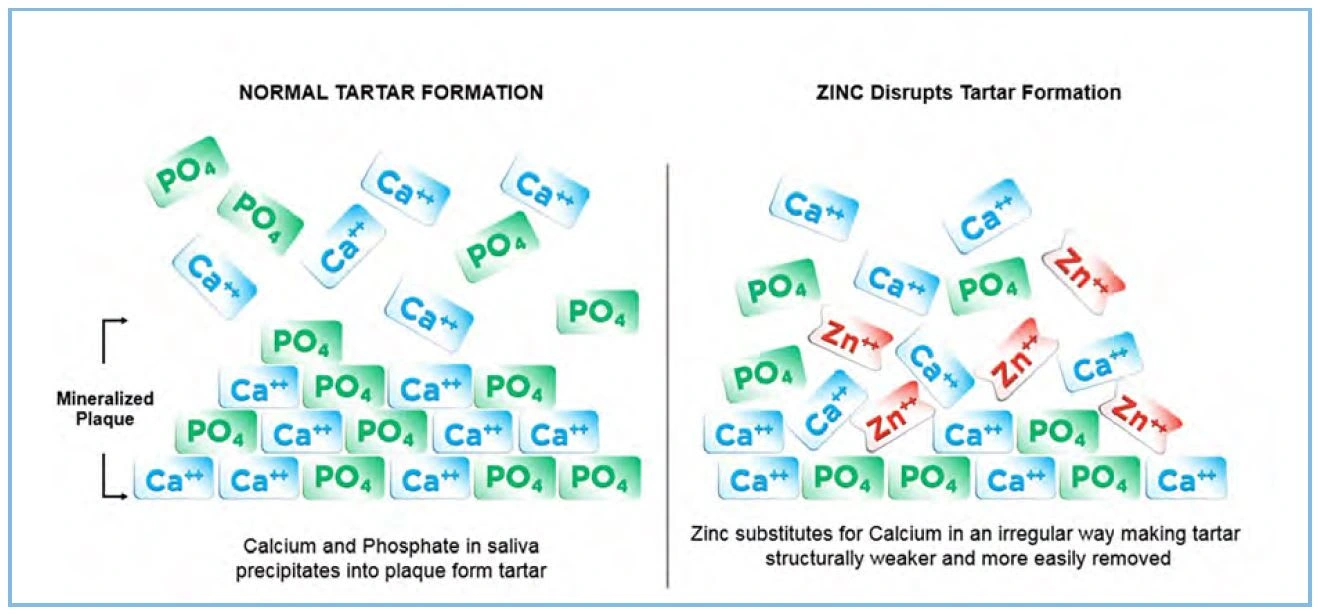

In the 2-step and smooth texture formulas, the positively charged zinc ion (Zn2+) inhibits crystal growth by substituting for calcium in the crystal lattice of calcium phosphate (Figure 22). This interferes with the crystal formation and slows crystal growth (Segreto et al. 1991). Stannous fluoride also inhibits plaque formation, which is the structure on which calcium and phosphate precipitate.

In the 2-step and smooth texture formulas, the positively charged zinc ion (Zn2+) inhibits crystal growth by substituting for calcium in the crystal lattice of calcium phosphate (Figure 22). This interferes with the crystal formation and slows crystal growth (Segreto et al. 1991). Stannous fluoride also inhibits plaque formation, which is the structure on which calcium and phosphate precipitate.

Figure 22. Mechanism of action of zinc

Figure 22. Mechanism of action of zinc